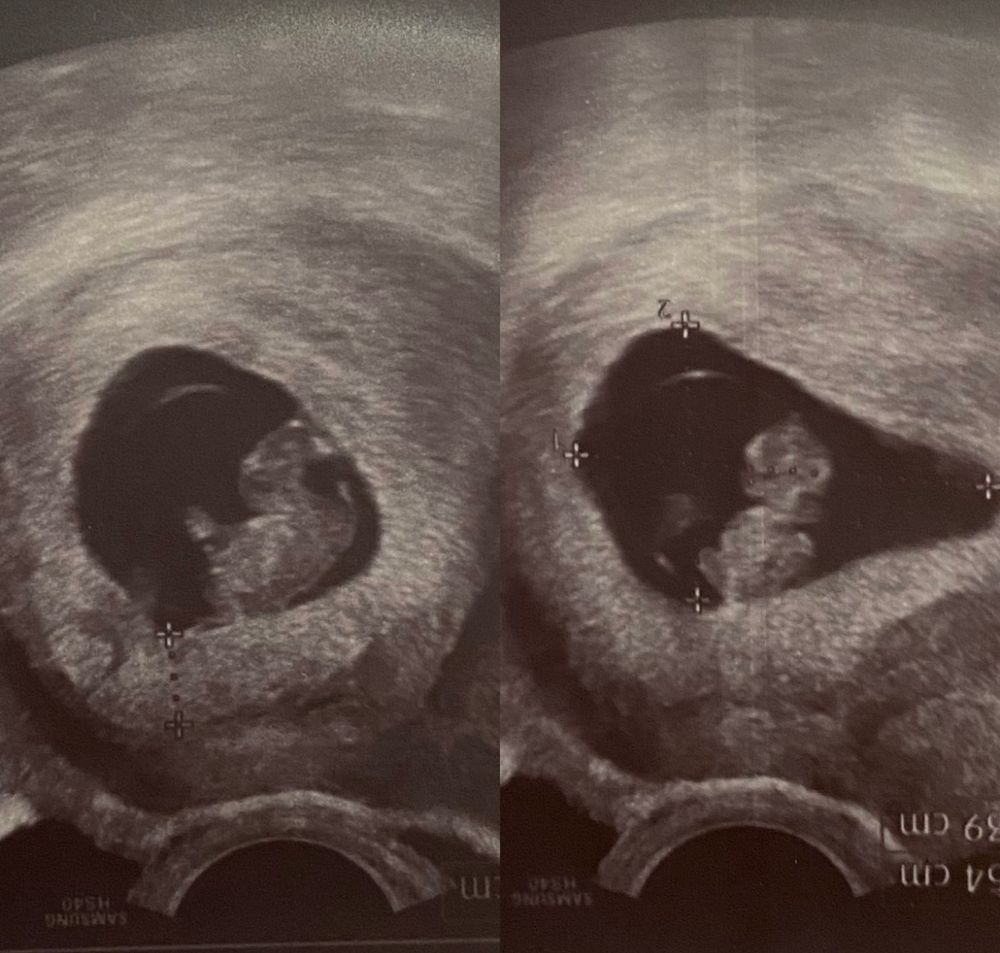

В 8 недель мой инопланетяшка, сердце прослушивалось